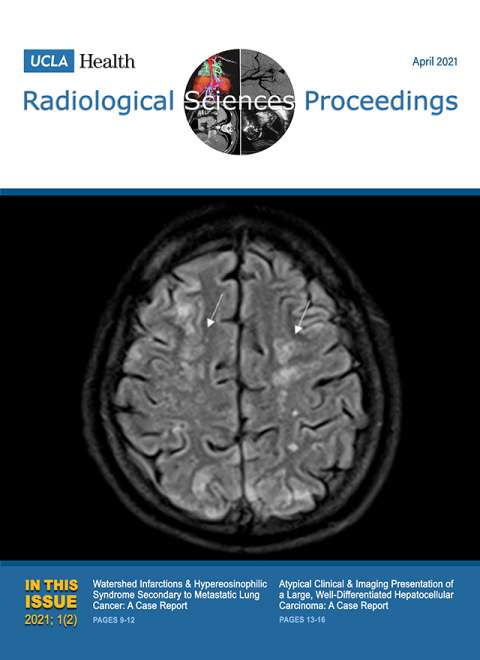

January 2021

Volume 1, Issue 1

- Giant Hepatic Regenerative Nodule in a 17-year-old with Alagille Syndrome

- Closed Sagittal Band Injury: A Case Report.

October 2021

Volume 1, Issue 4

- Electronic Integrated Diagnostic Report for Presenting Results of Breast Imaging and Breast Biopsy

- Iatrogenic Axillary Pseudoaneurysm Caused by Ultrasound-guided, Vacuum-assisted Biopsy of the Axillary Lymph Node: A Case Report

- Emergency Intravascular Aortic and Iliac Artery Lithotripsy to Facilitate Thoracic Endovascular Aortic Repair of a Ruptured Thoracic Aortic Aneurysm: A Case Report

- Acute Large Bowel Obstruction due to Pelvic Endometriosis: A Case Report